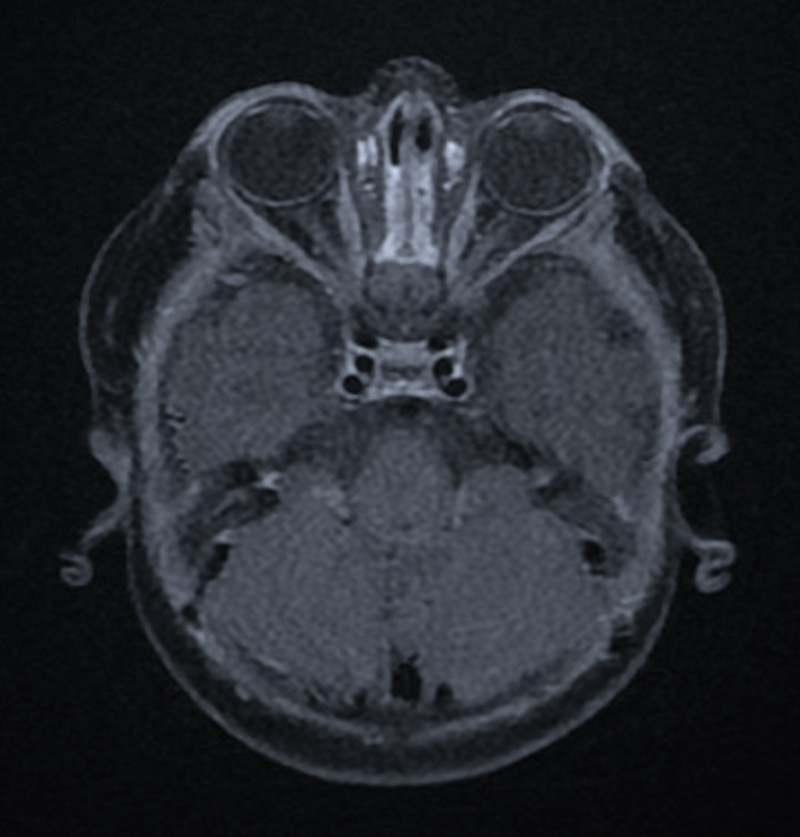

Case description: A 7-month-old male with a family history of osteopetrosis presented with hepatosplenomegaly. The infant was diagnosed with osteopetrosis based on radiological findings and genetic testing. Ophthalmologic examination and magnetic resonance imaging showed evidence of bilateral optic nerve compression. Endoscopic transcaruncular optic nerve decompression was not attainable The patient underwent a bilateral expanded endoscopic endonasal medial orbital wall and optic canal decompression.